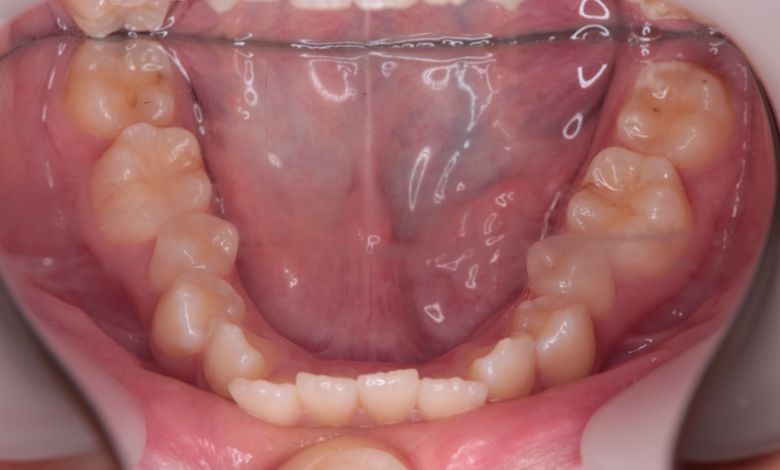

下の前歯が3本、強く重なり合って生えており、歯並びの乱れが目立つ

下顎の歯列では、前歯部に強い重なりが見られ、中切歯および側切歯がねじれたり前後にずれて生えているのが確認できる

術前に認められた前歯3本の強い重なりは完全に解消され、スムーズな歯列が形成されました。

精密検査の結果、抜歯を行わずに歯列弓を拡大する治療方針を選択。歯が正しい位置に並ぶスペースを

確保したことで、歯列は自然なU字型に整い、叢生が解消されました。見た目の改善だけでなく、

咀嚼機能の向上や清掃性の改善といった機能面での効果も期待できます。